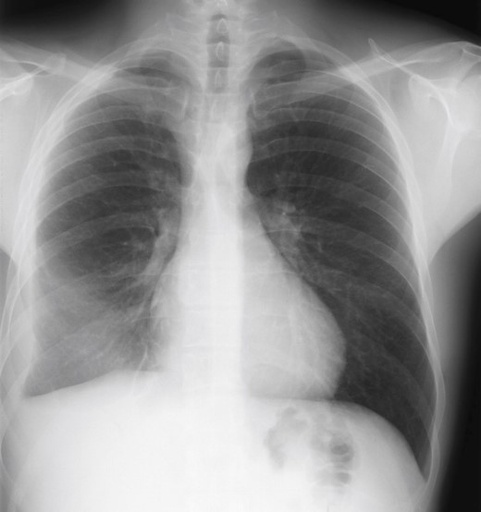

Imagerie du thorax

E. COCHE - UCL

Année académique 2025 - 2026

IPL - manipulateurs en imagerie

Cardio-thoracique

Poumon